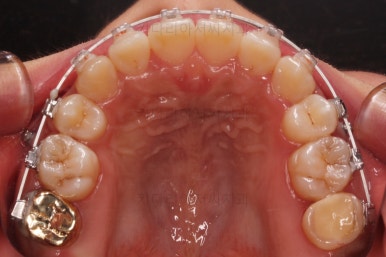

윗니만 추가적으로 발치를 1개 더 했어요.

아랫니는 최대한 추가 발치 없이 후방의 송곳니를 당겨와서 앞니 역할을 하게 했습니다.(총 4개 앞니처럼)

부분적으로 장치 셋팅을 다시 해줬고요.

밀고 당기기를 위해서 미니스크류를 셋팅했고요.

교합과 중앙선 및 디테일을 맞춰 나갑니다.

중앙선, 교합, 앞니 맞물림 등 모든 것이 좋아졌네요.